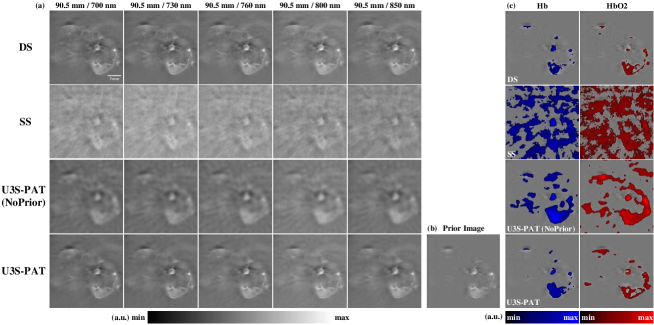

4.2 Spectral unmixing results

Fig.7 shows the image reconstruction and spectral un-mixing results of the in vivo animal experiment with . The images reconstructed by different methods are depicted in Fig.7 (a). Analysis of the images reconstructed using the SS and U3S-PAT (NoPrior) methods reveals the presence of numerous artifacts, attributable to inadequate measurement angle and the absence of prior constraints. In contrast, the images obtained with the U3S-PAT method exhibit cleaner results, closely resembling the DS image. Fig.7 (c) illustrates the distribution images of and , obtained by applying the linear spectral unmixing algorithm to each set of images. The spectral unmixing outcomes highlight the influence of artifacts in the reconstructed images on the unmixing accuracy. The results achieved by the U3S-PAT method align closely with the DS method, enabling clear differentiation of the distributions of and along organ contours.

The quantitative evaluation of the spectral unmixing experimental results is presented in Table II. The results demonstrate that the U3S-PAT method outperforms other methods in terms of PSNR, SSIM, and Dice metrics: compared to the SS method, the PSNR and SSIM increased for 100.50 and 27.00, respectively, and the Hb-Dice and HbO2-Dice increased for 202.39 and 320.59, respectively.